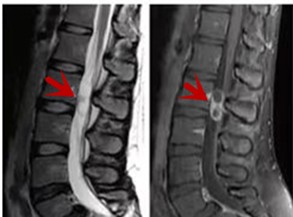

利器三:MRI(核磁共振)

MRI利于磁場和射頻脈沖使體內(nèi)的氫原子核發(fā)生磁共振現(xiàn)象而產(chǎn)生的圖像,對軟組織的分辨率很高,對于脊髓、椎間盤、神經(jīng)、血管、韌帶、骨髓、腰部肌肉及周圍軟組織有很好的顯示效果,可以清晰的顯示腰椎間盤突出對硬膜囊、神經(jīng)根壓迫程度,以及骨折是陳舊還是新鮮,同時在脊髓病變(如脊髓損傷、髓內(nèi)出血或腫瘤)、椎管內(nèi)膿腫/血腫、椎旁肌肉軟組織病變等方面也具有優(yōu)勢,但是檢查時間較長,部分患者可能因體內(nèi)金屬植入物(如心臟起搏器、人工耳蝸等)而無法進(jìn)行檢查。

箭頭提示腰椎管內(nèi)腫瘤

紅色箭頭提示新鮮骨折,黃色箭頭提示陳舊性骨折